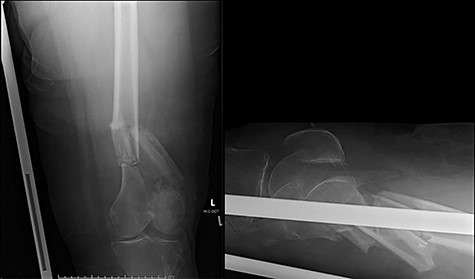

Case 3 (Figs 6 and 7): another case of fatigue fracture of the plate prior to bony union. Here cerclage wires close to the fracture site may have had the same effect as placing screws immediately adjacent to the fracture. It would seem reasonable to speculate that their exclusion may have led to a more satisfactory outcome.